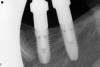

7rivers Опубликовано 11 апреля, 2010 Поделиться Опубликовано 11 апреля, 2010 Уважаемые коллеги, подскажите, если не трудно.Установил 2 импланта, первичная стабилизация номальная, но на ортопане одну заглушку не докрутил. Через три месяца, под недокрученой заглушкой проросла слизистая,выпилил керамическим триммером, установил формирователи десны. Начал устанавливать через 2 недели трансферы для открытой ложки имплантов titanium fix. Один качается. Сделал снимок, на снимке не досажен. Еще раз прошелся триммером по кромке импланта поменял трансферы местами, повторил снимок, все равно не досажен, хоть и меньше. Но внутри импланта вымыл хорошо, слизистой нет.Как можно еще очистить? Почему не садится? Имплант может быть не точным? При сравнении трансфера с аналогами имплантов по ощущениям разница есть.Спасибо. Ссылка на комментарий

7rivers Опубликовано 16 апреля, 2010 Автор Поделиться Опубликовано 16 апреля, 2010 Спасибо всем за помощь. Как и сказали, нависающий край был причиной недосадки трансфера.С начала по совету уважаемого Bier,снял кромку трансфера,но мало,на снимке видно не доходит,больше пилить не стал.Фрезы с пином для снятия навесов,которую подсказал уважаемый Sahan,у нас в наборах нет,буду искать.Взял обратный конус твердосплавный и прошелся по медиально-язычной границе импланта,жалко кость конечно.Все село,трансферы поменял местами,на снимке видно.Импланты кручу недавно.До этого ставил астру,шейка в виде песочных часов в аналогичной ситуации проблем не создавала.А тут еще директор смутил,говорит на бразильских бывает не соответствие.Спасибо огромное за практические советы. Doc скажите пожалуйста,а чем вы снимаете костный навес. Ссылка на комментарий